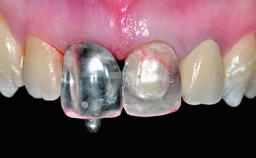

A 32-year-old female Caucasian patient with a compromised maxillary right central incisor was referred to us by a general dentist. Her chief complaints were discomfort and mobility of tooth 11 with unsatisfactory esthetics due to discoloration. The patient reported a previous trauma, some years earlier, as the origin of pathology on the afflicted tooth. Anamnesis was negative for any other dental or periodontal pathology in the remaining dentition. The patient did not take any medication and reported to be a light smoker (5–10 cigs/day). She had high esthetic expectations of her treatment. The extraoral examination revealed a high smile line with full exposure of her maxillary teeth and surrounding soft tissue in the area between the second premolars.

Interim Prosthesis during Healing Fixed Fixed